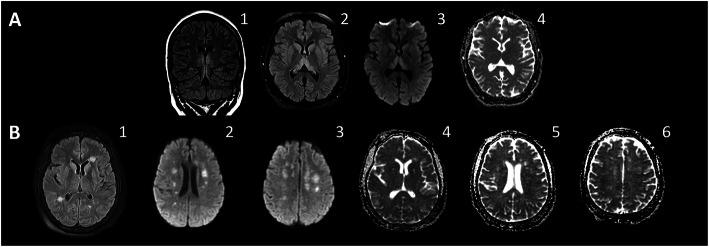

Coronavirus disease 2019 (COVID-19) is a highly infectious pandemic caused by a novel coronavirus called severe acute respiratory syndrome coronavirus 2 (SARS-CoV-2). It frequently presents with unremitting fever, hypoxemic respiratory failure, and systemic complications (e.g., gastrointestinal, renal, cardiac, and hepatic involvement), encephalopathy, and thrombotic events. The respiratory symptoms are similar to those accompanying other genetically related beta-coronaviruses (CoVs) such as severe acute respiratory syndrome CoV (SARS-CoV) and Middle East Respiratory Syndrome CoV (MERS-CoV). Hypoxemic respiratory symptoms can rapidly progress to Acute Respiratory Distress Syndrome (ARDS) and secondary hemophagocytic lymphohistiocytosis, leading to multi-organ system dysfunction syndrome. Severe cases are typically associated with aberrant and excessive inflammatory responses. These include significant systemic upregulation of cytokines, chemokines, and pro-inflammatory mediators, associated with increased acute-phase proteins (APPs) production such as hyperferritinemia and elevated C-reactive protein (CRP), as well as lymphocytopenia. The neurological complications of SARS-CoV-2 infection are high among those with severe and critical illnesses. This review highlights the central nervous system (CNS) complications associated with COVID-19 attributed to primary CNS involvement due to rare direct neuroinvasion and more commonly secondary CNS sequelae due to exuberant systemic innate-mediated hyper-inflammation. It also provides a theoretical integration of clinical and experimental data to elucidate the pathogenesis of these disorders. Specifically, how systemic hyper-inflammation provoked by maladaptive innate immunity may impair neurovascular endothelial function, disrupt BBB, activate CNS innate immune signaling pathways, and induce para-infectious autoimmunity, potentially contributing to the CNS complications associated with SARS-CoV-2 infection. Direct viral infection of the brain parenchyma causing encephalitis, possibly with concurrent neurovascular endotheliitis and CNS renin angiotensin system (RAS) dysregulation, is also reviewed.